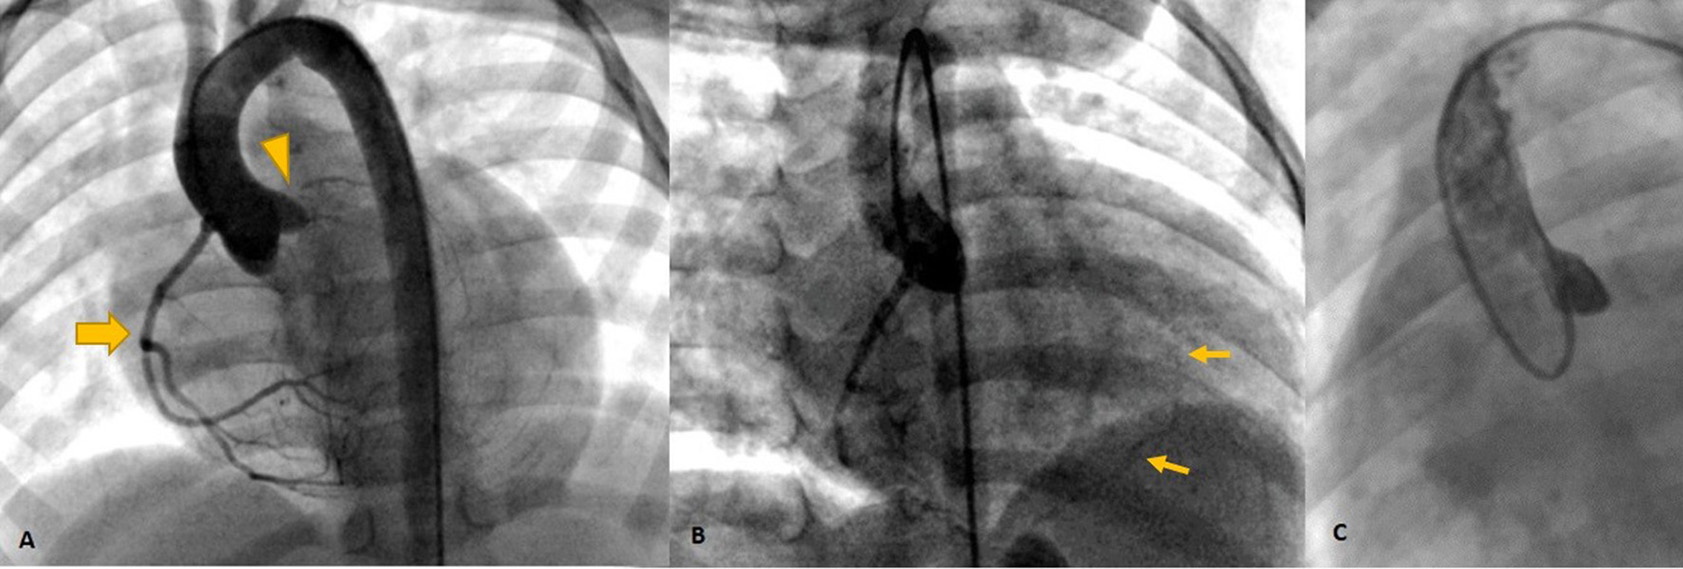

Cardiac magnetic resonance was performed to investigate the possible underlying pathology, which confirmed severe LV dilation, severely reduced systolic function (LVEF: 22%), and severe MR (Figure 2). Late gadolinium enhancement (LGE) sequence demonstrated subendocardial to transmural scar in the basal and especially at the mid anterior and anteroseptal segments, raising suspicion of an ischemic insult. Gated CT coronary angiography (Figure 3) demonstrated an absent LM stem with a centripetal filling of the small caliber confluent LAD and circumflex, likely from collaterals from a dilated right coronary artery. Angiography confirmed the LM atresia with a retrograde collateral filling of LAD and LCX arteries from a dominant RCA. There was no connection to the pulmonary arterial branches (Figure 4; Supplementary Videos 1, 2). Considering the extent of myocardial fibrosis, small-sized coronary arteries and LV remodeling were required, and according to the decision of heart team specialists, the patient underwent medical treatment for heart failure and was scheduled for a heart transplant.

Figure 4

Invasive angiography (A–C) showing the dominant RCA [Thick arrow in (A)] retrogradely filling the left system via collaterals [Thin arrows in (B)] and no antegrade flow in left cusp injection (C) confirming left main atresia (arrowhead).